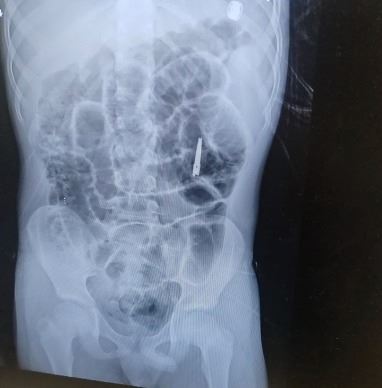

בשבוע שעבר, בשעות הלילה המאוחרות, הגיע י' יחד עם משפחתו למלר"ד ילדים במרכז הרפואי שערי צדק לאחר שבלע להבי מספריים באורך של שלושה ס"מ. לאחר צילום הרנגטן בו נראו המספריים כאשר הלהבים נמצאים במצב פתוח בקיבה, הוזעקו צוותים רפואיים בתחומי כירורגיית וגסטרו ילדים, לרבות מומחה לפרוצדורות אנדוסקופיות בילדים בשערי צדק, ד"ר אורן לדר, והוחלט להכניס את י' לחדר הניתוח באופן דחוף כדי להוציא את המספרים.

כשי' נמצא בהרדמה מלאה בחדר הניתוח, בוצע צילום נוסף כדי לבחון את מיקום ומצב המספרים. בצילום התברר כי המספריים נסגרו מעצמם, עברו את הקיבה והגיעו לעומק המעי הדק. "הייתה סכנה שהמספריים הפתוחים יגרמו לפציעה לושט או לקיבה ורצינו לבצע בדיקה על מנת לאתר ולשלוף אותם", אומרת ד"ר אסתר אורלינסקי-מאייר, מומחית בגסטרואנטרולוגיה ילדים בשערי צדק. "באורח פלא ומסיבה לא ברורה, ראינו שהמספריים נסגרו מעצמם, כך שהסכנה לפציעה בדרכי העיכול פחתה".

בתמונות:

צילום המספריים במצב פתוח בקיבה ובמצב סגור במעי הדק.